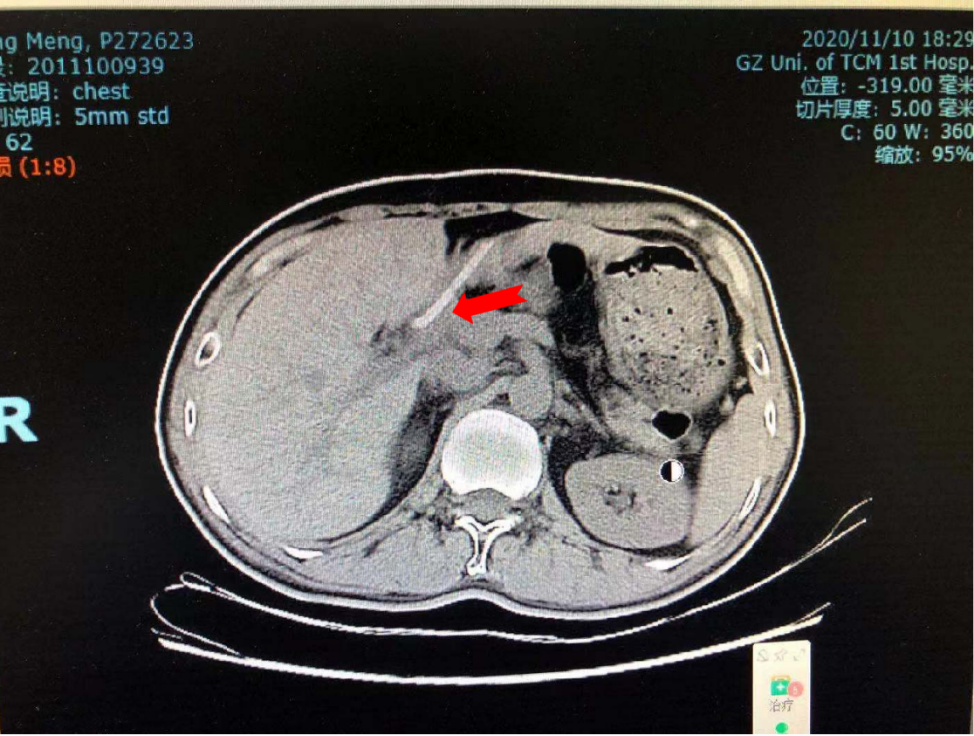

1、患者十二指肠壶腹Ca根治术后6年余,未见肿瘤复发。

治疗后:2020年11月10日复查CT示:1.左上肺局部肺大疱,左上肺前段小结节,较前相仿,考虑良性可能性大。2.十二指肠壶腹Ca根治术后改变,胰管内支架移动至十二指肠内。左肾上腺结节较前变化不大,考虑增生性结节可能。肝脏多发囊肿。